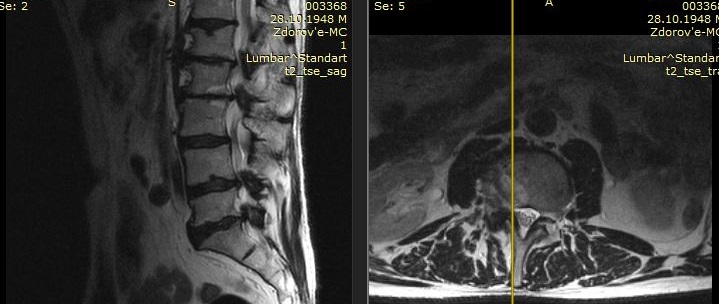

Рис - Многоуровневый стеноз МРТ до операцииРис - Многоуровневый стеноз КТ после операции